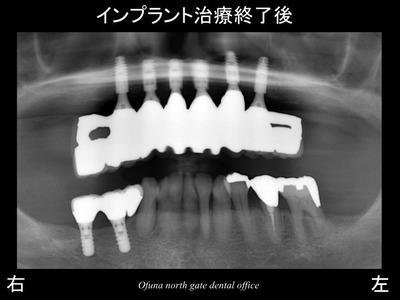

以下は、インプラント埋入後です。

治療期間中は、固定式の仮歯 を使用していただきます。

手術後の時点では、1本のインプラント(左から3番目)は骨との安定が悪いため、

インプラントの土台 は使用しない状態としました。

骨との安定(結合)を待ち型取りとなります。

それまでは、固定式の仮歯となりますので、噛めないということはありません。

このようなケースは、治療後も綿密なケアーを行っていくことが重要です。

使用したインプラントは、アンキロス インプラント です。

前歯部に適したインプラント(プラットホーム・スイッチング) となっています。